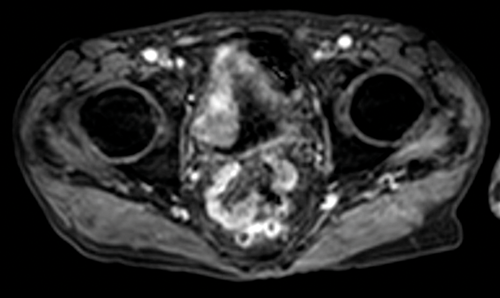

Figure 1. T1 MRI showing left lateral bladder tumour seen as intermediate signal compared with low signal urine in the bladder. There is fat stranding adjacent to the tumour, in keeping with early T3b disease.

T1 sequences are useful for identifying the primary tumour, as it can be seen against the dark urine in the bladder (Figure 1). T1 sequences are valuable for assessing perivesical fat infiltration as the fat adjacent to the bladder is of high signal. T1 sequences are also useful for assessment of nodal disease or bone metastases.

Figure 5. Contrast enhanced image of the same patient as Figure 1 shows full

thickness enhancement of the bladder wall and enhancement of the distal left ureter.